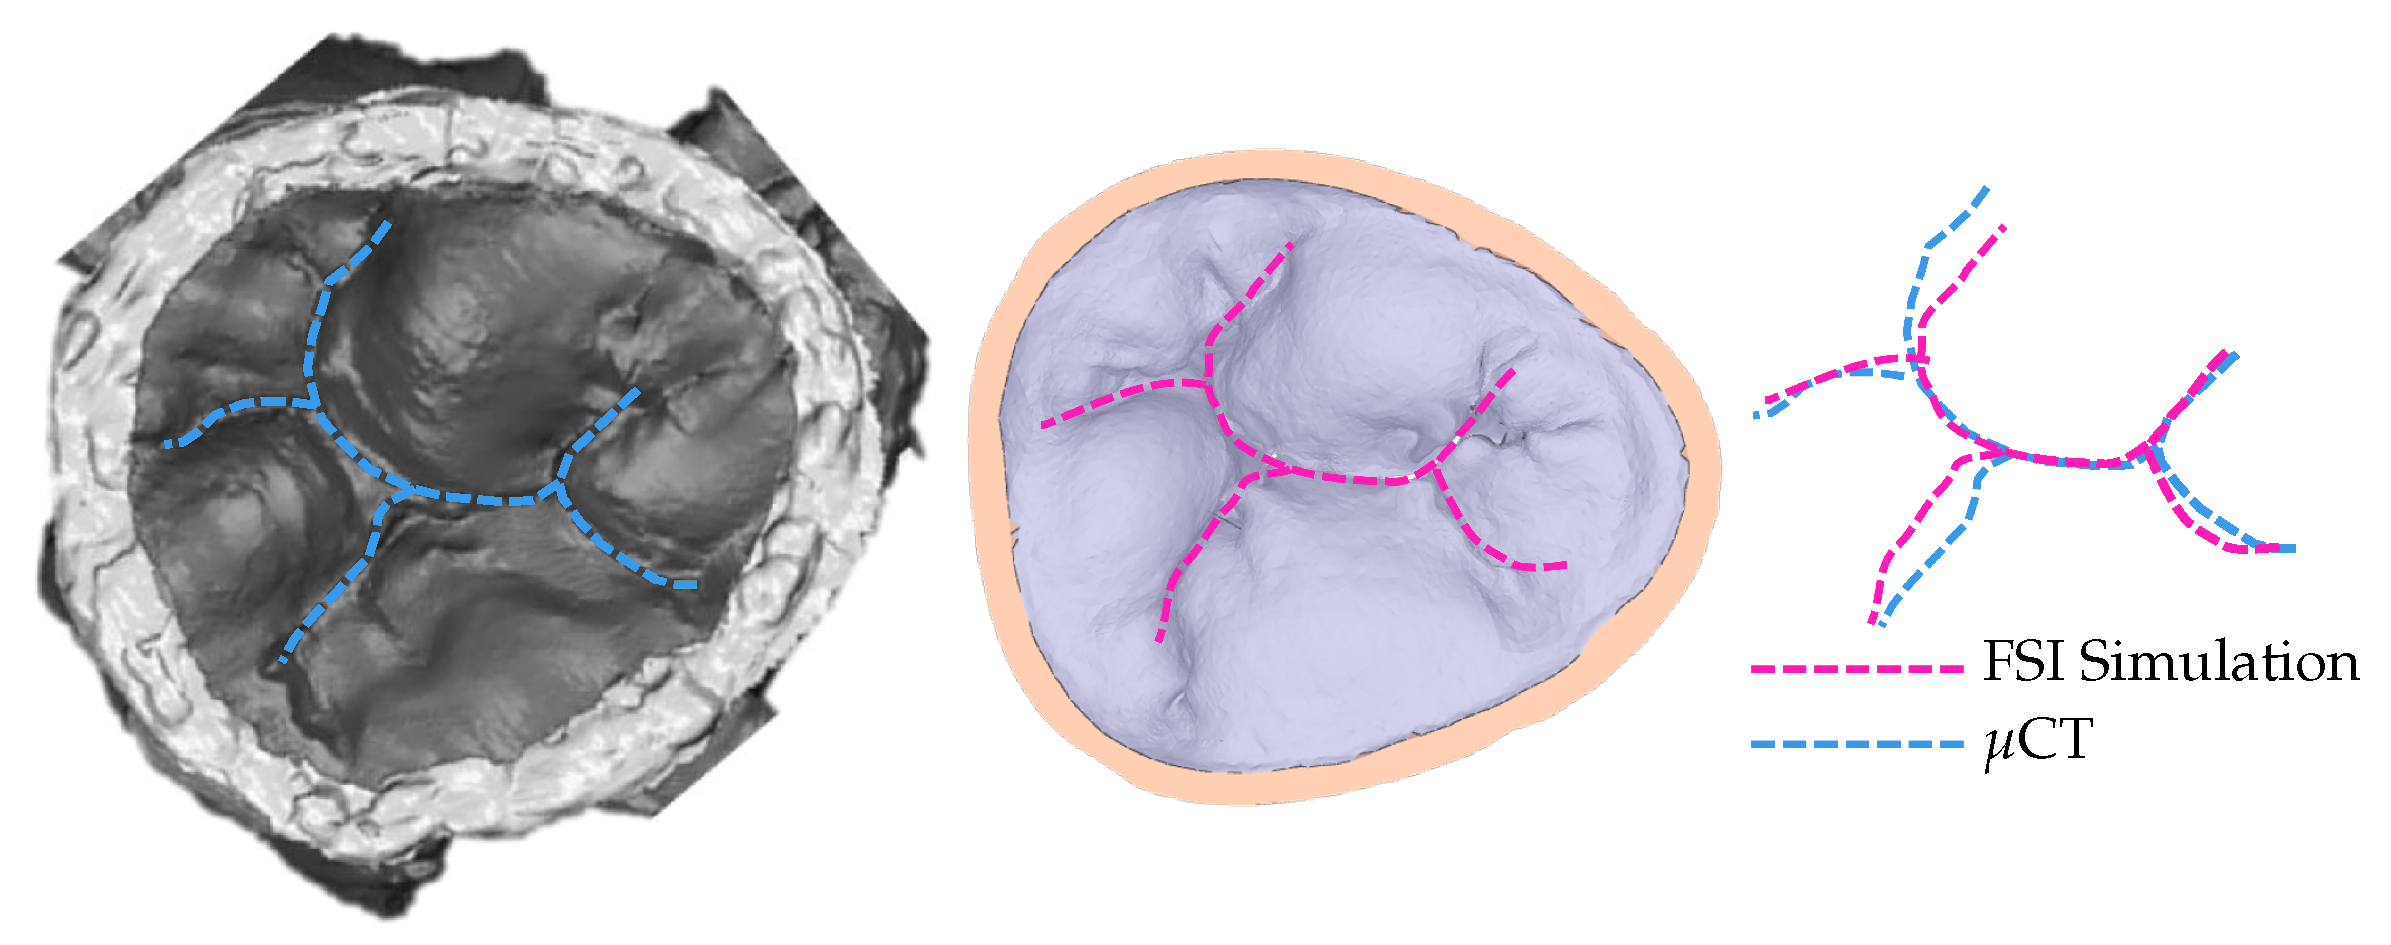

To confirm that the achieved simulated closure, using the model with 30% elongation compared to the original model, matches the closure observed in experimental settings, the coaptation lines are compared (Figure 5). The same material property values are used for the entire model. Multiple, more precise material properties prescribed to appropriate parts of the model would yield coaptation lines with even better match [13].

Figure 5.

Coaptation lines from μCT of closed HV and computational simulation are used to validate the resulting simulated closure. To achieve this closure, the model with 30% elongation, shown in Figure 3, is used.